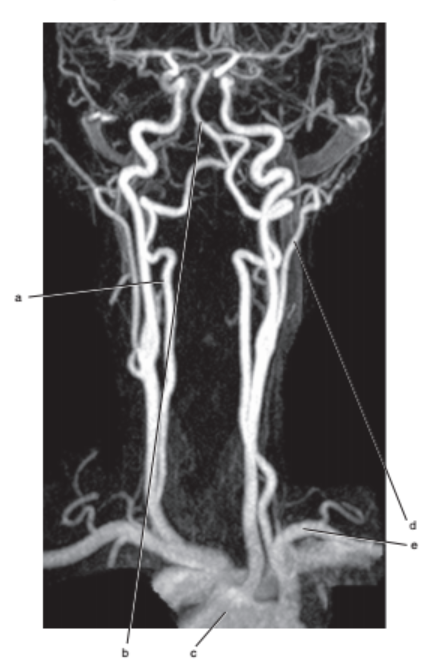

What is letter l ?

Common carotid

What is letter e ?

Subclavian artery

What is letter a ?

Vertebral artery

What is letter c ?

Aortic arch

What is letter b ?

Thyroid gland

Internal jugular vein

External carotid artery